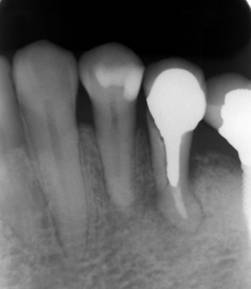

インプラントの隣の歯が破折し腫れていました

抜歯後6か月

抜歯部位にインプラントを追加しました。CBCT

上部構造もやり替えてジルコニア連結冠にしました

他院で治療されていたケース。隣の歯が割れています。その隣も根の先に病巣があり抜歯せざるを得ませんでした。

破折線が見えています

既存のインプラントの上部構造(クラウン)を天然歯と同じように形成しブリッジの支台としました。上部構造はフルジルコニアのブリッジ。

一年後